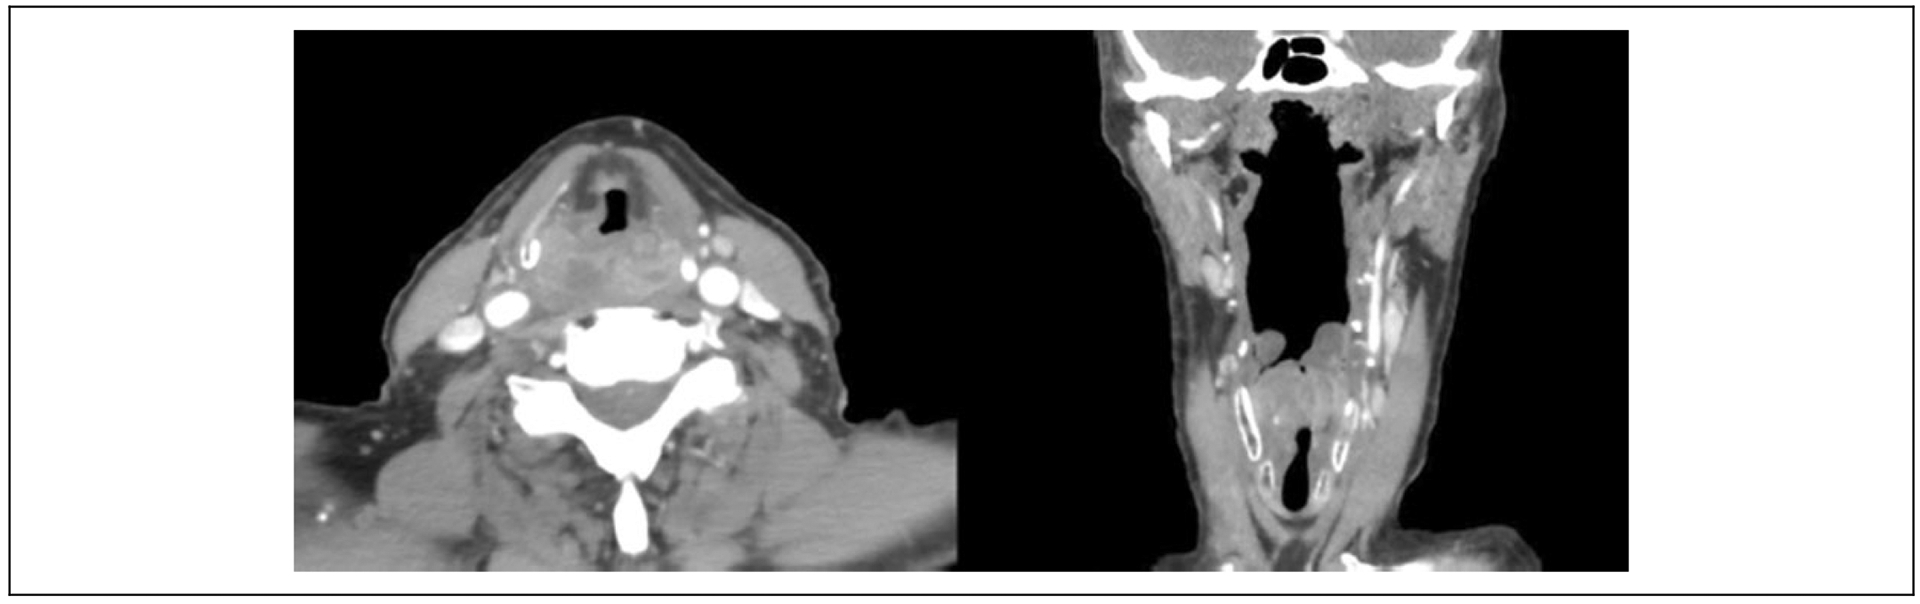

The patient is a 74-year-old male with a 1 pack per day smoking history for 60 years who presented with a reported 20-pound weight loss, dysphagia, and dysphonia progressing over the course of 6 months, the weight loss occurring in the absence of effort. On initial evaluation in the emergency department, he was noted to have a rightward anterior deviation of the arytenoid complex with a hypomobile right vocal fold. There appeared to be a posterior commissure thickening imposing on the glottic airway. A subsequent computed tomography scan (Figure 1) showed a 3.5 cm × 1.8 × cm 2.1 cm mass in the hypopharynx with mass effect displacing the glottic airway anteriorly. Given the high likelihood of malignancy, the patient was scheduled for direct laryngoscopy and biopsy of the hypopharyngeal mass, as well as gastrostomy tube placement. From the operating room, an initial frozen section of the right postcricoid mass was concerning for squamous cell carcinoma in situ and specimens were sent for permanent pathology. Multidisciplinary evaluation of this patient with presumed T3N0M0 squamous cell carcinoma of the hypopharynx yielded a consensus recommendation for upfront surgery, including total laryngopharyngectomy and bilateral neck dissections, including a free flap reconstruction with postoperative adjuvant treatment pending for the final pathologic examination of the biopsy material.

Figure 1.

Computed tomography scan of hypopharyngeal mass showing right-sided 3.5-cm partially cystic mass, with mass effect displacing glottic airway anteriorly.